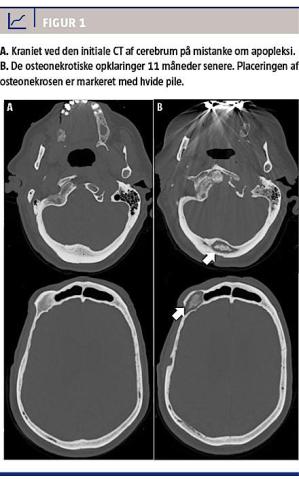

I efterforløbet dannedes der fistler omkring cikatricen og over højre øje, hvorfra der aldrig var biopteret. Patienten havde da haft generende kraniesmerter i 11 måneder og undervejs fået foretaget tre MR-skanninger af cerebrum, to CT’er af cerebrum, en knoglescintigrafi og en PET-CT, som alle viste progredierende osteolytisk osteonekrose flere steder i kraniet (Figur 1). Ydermere var der foretaget flere CT’er af thorax-abdomen og UL-skanning af abdomen, hvor man fandt normale forhold fraset den kendte coloncancer. Mistanken om metastasering fra hhv. prostatacanceren og coloncanceren ansås for at være afkræftet i kraft af de tre negative patologisvar. Behandlingsmæssigt valgte man en afventende strategi, da patientens gener kom fra fistelsekretionen. Hovedpinen var nu sparsom og aftagende, og der var en fortsat bedring i almentilstanden. Andre differentialdiagnoser var derfor aktuelle, herunder specielt prednisolonudløst aseptisk osteonekrose, overset malignitet, morbus Paget, aseptisk osteomyelitis og mange flere.

Der findes mange differentialdiagnoser til osteonekrose (Tabel 1). Højdosissteroidbehandling, som patienten fik i forbindelse med mistanken om arteritis temporale er kendt for at kunne medføre avaskulær osteonekrose [1]. Lidelsen findes ofte i de vægtbærende knogler med præference for specielt hofteleddet, hvorfor en fremkomst i kraniet ville være sjælden [2]. Steroidinduceret osteonekrose fører til trabekulær kollaps af den spongiøse knoglestruktur [3]. Dette stemmer ikke overens med patientens kranieopklaringer, da disse var af ekspansiv karakter (Figur 1).